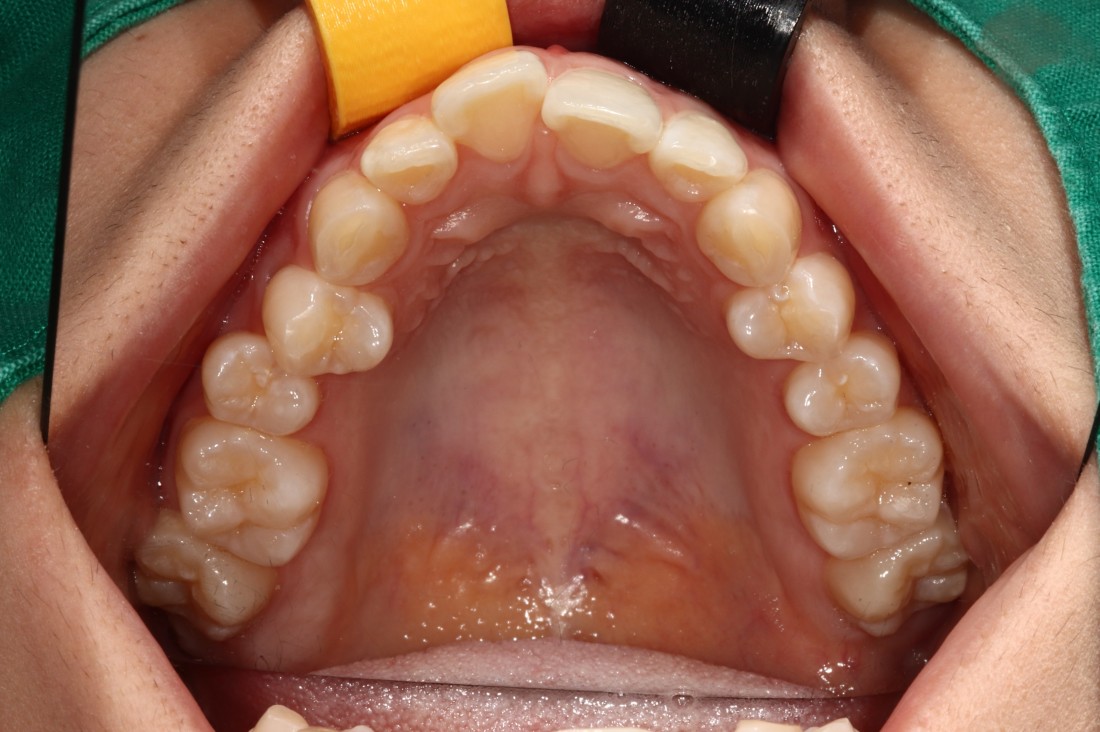

광주 교정치과

충치치료 + 치아교정 동시 케이스

광주 교정치과 추천하는 이유는

전문의 충치치료까지 동시에 가능하여

토탈 구강건강 관리를 받으실 수 있기 때문입니다.

5층은 일반진료센터,

4층은 VIP 치아교정실로 운영되어

치아교정 진료만을 담당하는

교정전담 의료진의 세심한 케어로

광주 교정치과를 추천합니다.